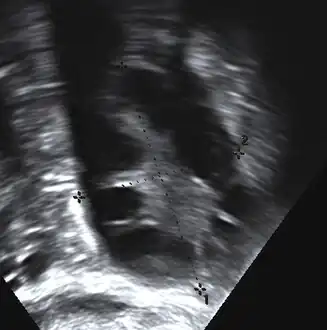

The syndrome acquired its most widely used name due to the common sign on ultrasound examination of multiple (poly) ovarian cysts. These "cysts" are in fact immature ovarian follicles. The follicles have developed from primordial follicles, but this development has stopped ("arrested") at an early stage, due to the disturbed ovarian function. The follicles may be oriented along the ovarian periphery, appearing as a 'string of pearls' on ultrasound examination.[86]

Transvaginal ultrasound scan of polycystic ovary

- Gynecologic ultrasonography, specifically looking for small ovarian follicles. These are believed to be the result of disturbed ovarian function with failed ovulation, reflected by the infrequent or absent menstruation that is typical of the condition. In a normal menstrual cycle, one egg is released from a dominant follicle – in essence, a cyst that bursts to release the egg. After ovulation, the follicle remnant is transformed into a progesterone-producing corpus luteum, which shrinks and disappears after approximately 12–14 days. In PCOS, there is a so-called "follicular arrest"; i.e., several follicles develop to a size of 5–7 mm, but not further. No single follicle reaches the preovulatory size (16 mm or more). According to the Rotterdam criteria, which are widely used for diagnosis of PCOS,[10] 12 or more small follicles should be seen in a suspect ovary on ultrasound examination.[21] More recent research suggests that there should be at least 25 follicles in an ovary to designate it as having polycystic ovarian morphology (PCOM) in women aged 18–35 years.[95] The follicles may be oriented in the periphery, giving the appearance of a 'string of pearls'.[96] If a high-resolution transvaginal ultrasonography machine is not available, an ovarian volume of at least 10 ml is regarded as an acceptable definition of having polycystic ovarian morphology. rather than follicle count.[95]

Ultrasound findings in PCOS include enlarged ovaries with peripheral follicles in a "string of pearls" configuration.